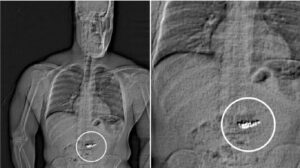

Un ladrón identificado como Jaytan Lawrence Gilder, de 32 años, se tragó pendientes de diamantes valorados en 769.000 dólares, de la marca Tiffany